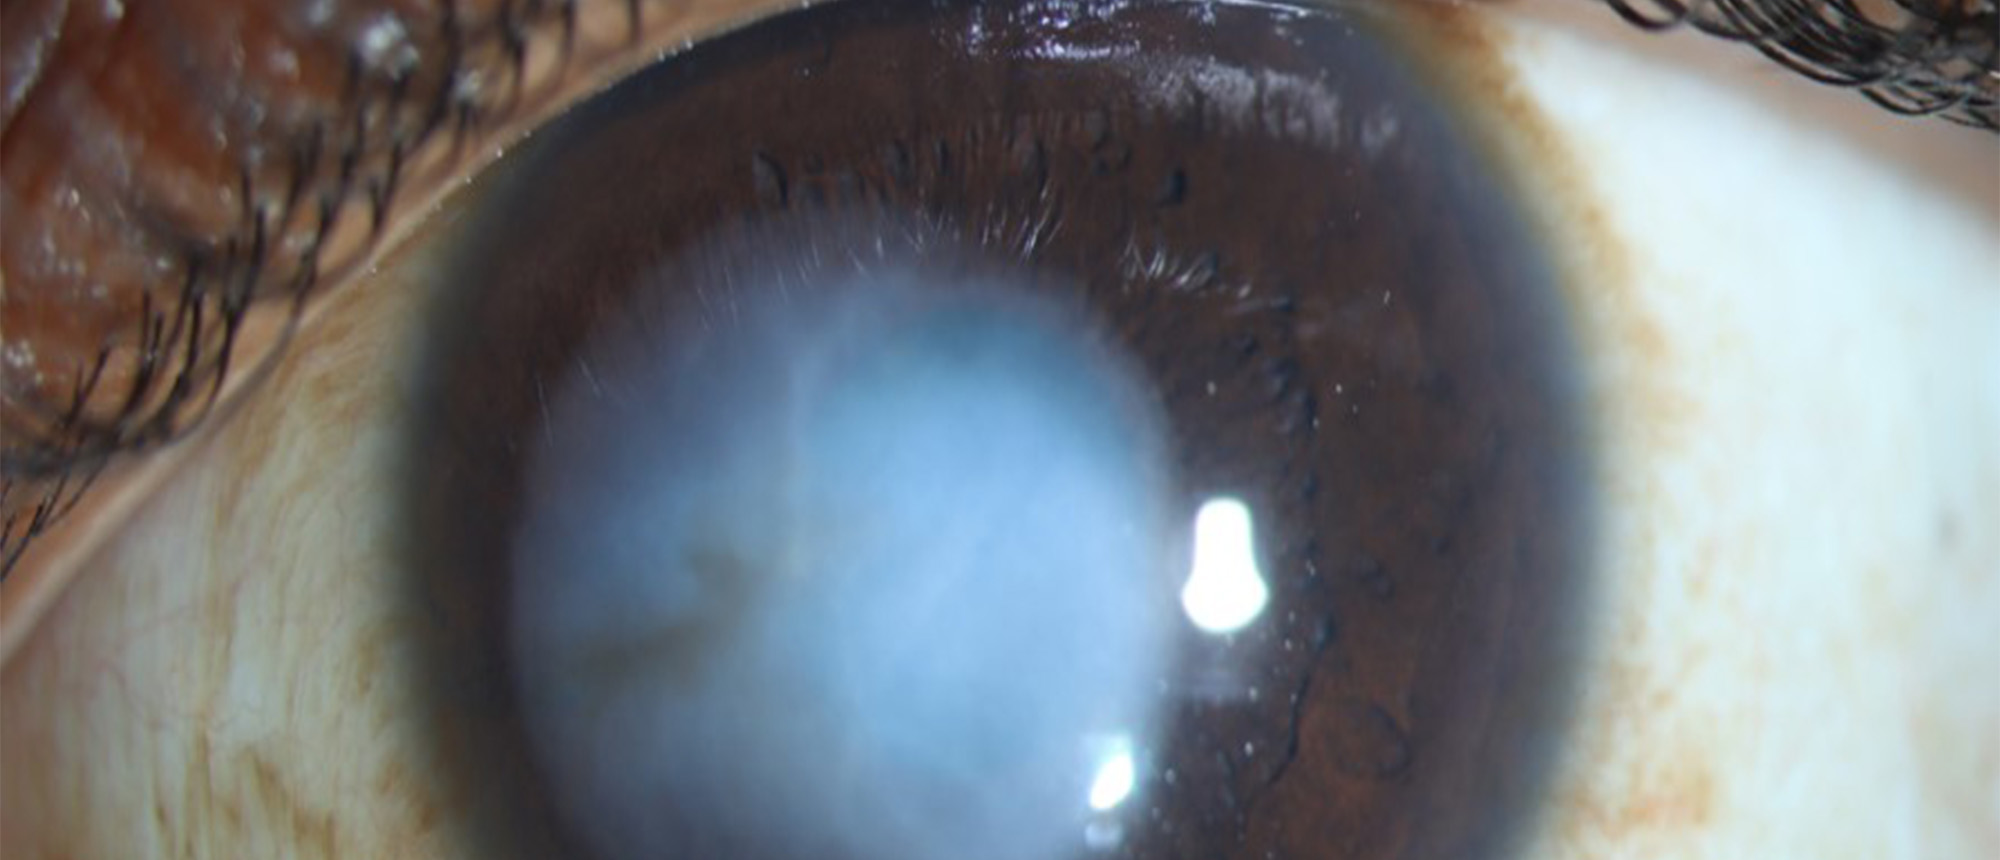

A patient with no past medical history and a past ocular history of five prior pterygium removal surgeries presented to the Bascom Palmer Emergency Room for pain and irritation in his right eye for 1 week. He endorsed working construction just prior to symptom onset, but denied any trauma to the ey…